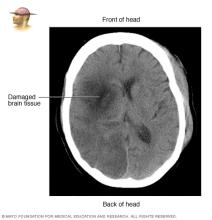

Brain tissue damaged by stroke

CT scan of brain tissue damaged by stroke

CT scan showing brain tissue damaged by stroke

During a stroke, things move quickly once you get to the hospital. Your emergency team works to learn what type of stroke you're having. You'll likely have a CT scan or other imaging test soon after arrival. Healthcare professionals also need to rule out other possible causes of your symptoms, such as a brain tumor or a drug reaction.

• Computerized tomography (CT) scan. A CT scan uses a series of X-rays to create a detailed image of your brain. A CT scan can show bleeding in the brain, an ischemic stroke, a tumor or other conditions. You might have a dye injected into your bloodstream to view the blood vessels in the neck and brain in greater detail. This type of test is called a computerized tomography angiography.